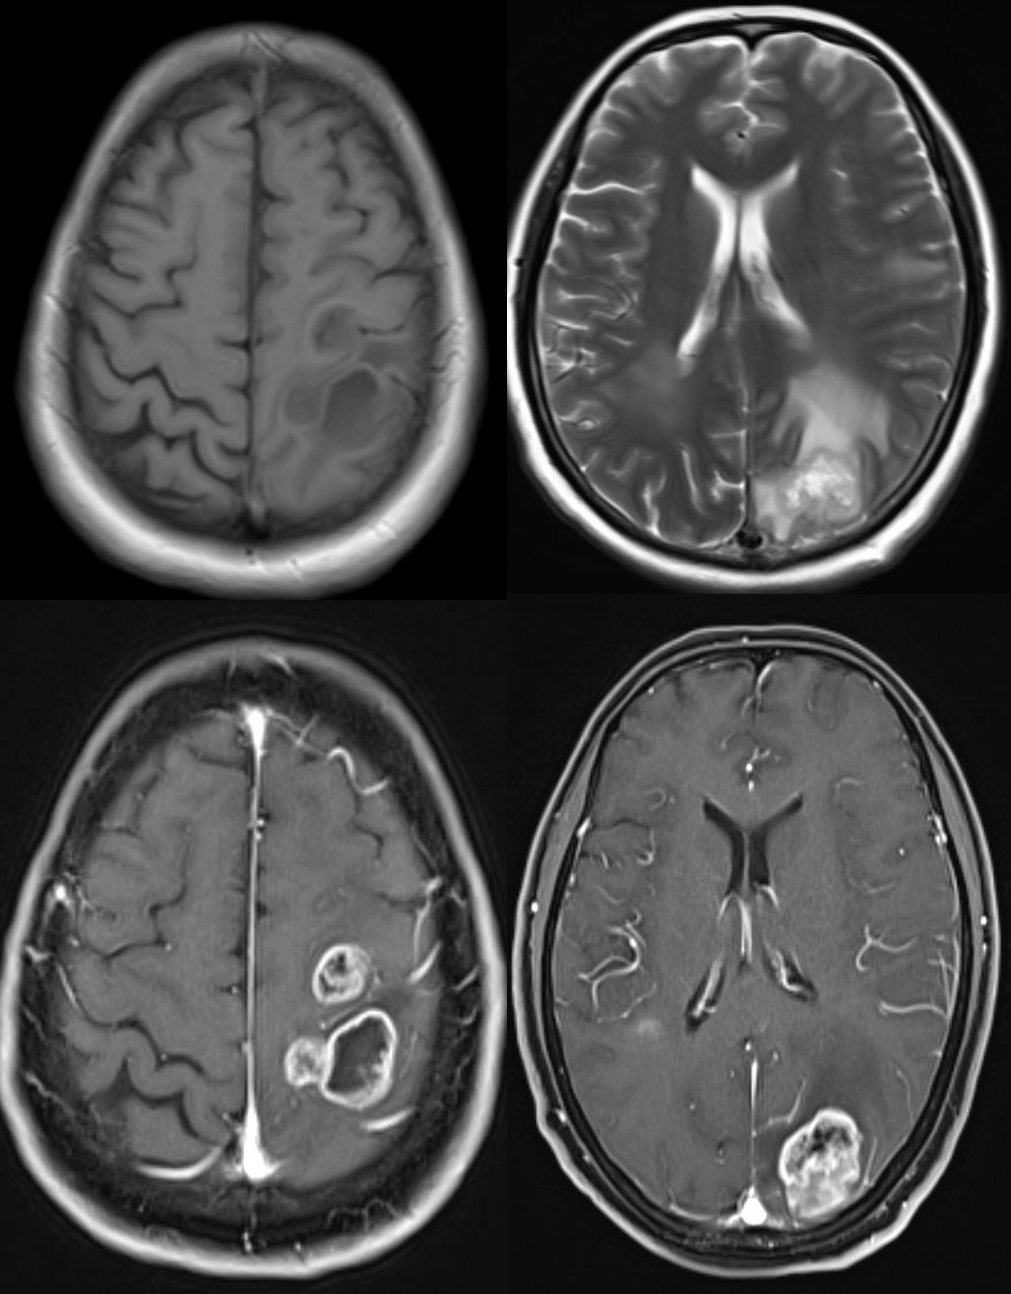

5. 术前误诊为淋巴瘤、转移瘤的颅内多发胚胎性肿瘤。

该患者男,19岁,因头痛头晕1个月前来就诊。头颅MRI示:幕上、幕下多发病变。术前诊断:转移瘤?淋巴瘤?行右侧颞叶脑立体定向活检术,病理提示:中枢胚胎性肿瘤。

中枢神经系统胚胎性肿瘤指有未分化或低分化的神经外胚层细胞形成的高度恶性的肿瘤,具有多向分化的潜能。该病比较少见,占中枢神经系统肿瘤的0.1%,好发于儿童和青少年。该病预后不良,明确诊断仍然依靠手术或活检。